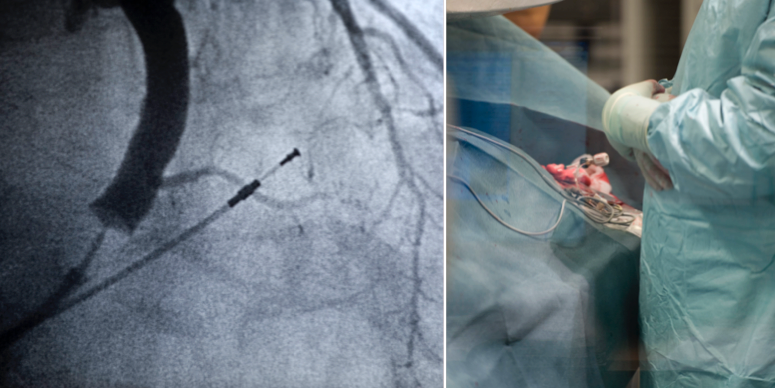

Arkivbilder (TT)

5 000 svenskar har fått undermåliga hjärtimplantat

Cirka 5 000 patienter befaras ha fått krånglande pacemakers och andra undermåliga hjärtprodukter inopererade, avslöjar SVT Nyheter.

Omkring 1 300 implantat har behövts opereras ut. Orsaken är att implantaten har gått sönder i förtid eller återkallats på grund av tekniska problem.

De undermåliga produkterna kan orsaka upprepade kraftiga elchocker rakt in i hjärtat.